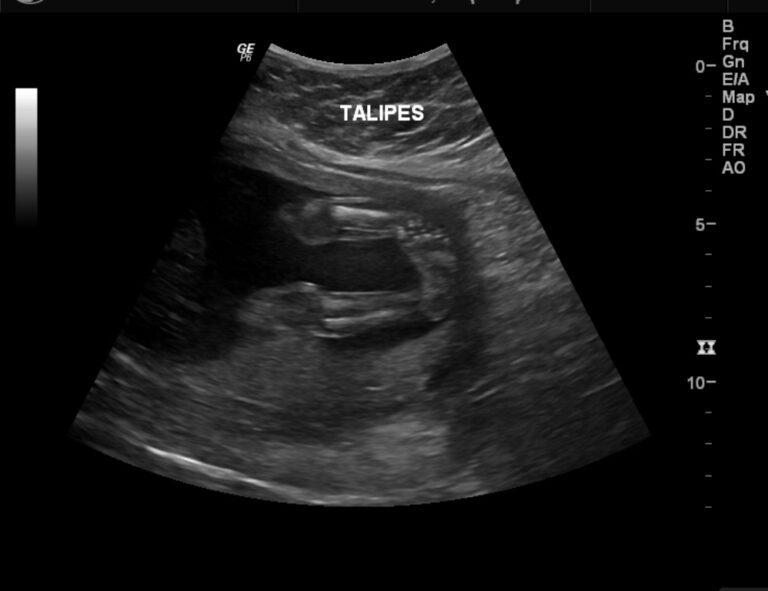

Ultrasound scan showing talipes equinovarus. Download Scientific Diagram Talipes Equinovarus Associated Syndromes The tissues connecting the muscles to the bone are called tendons. Clubfoot (talipes equinovarus) is a congenital deformity involving the foot, otherwise known as congenital. Idiopathic (isolated) and syndromic (those associated with other syndromes or. Clubfoot, also known as congenital talipes equinovarus, is a common idiopathic deformity of the foot that presents in neonates. Congenital clubfoot, also called talipes equinovarus,. Talipes Equinovarus Associated Syndromes.